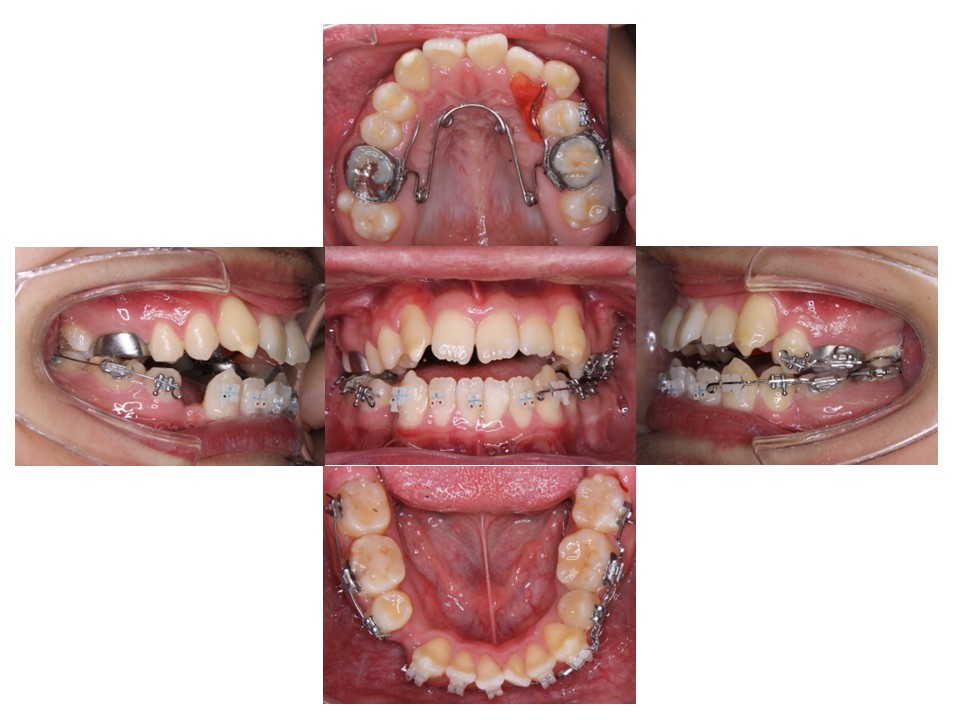

上あごの歯列の横幅を広げています